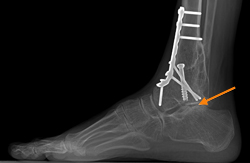

Over time, the increased stress that is placed on the rest of the foot after an ankle fusion can lead to arthritis of the joints surrounding the ankle. This patient had pain in the subtalar joint (arrow) and required an additional fusion of that joint to minimize the pain. Increased stress on other joints is the most concerning problem following ankle fusion.